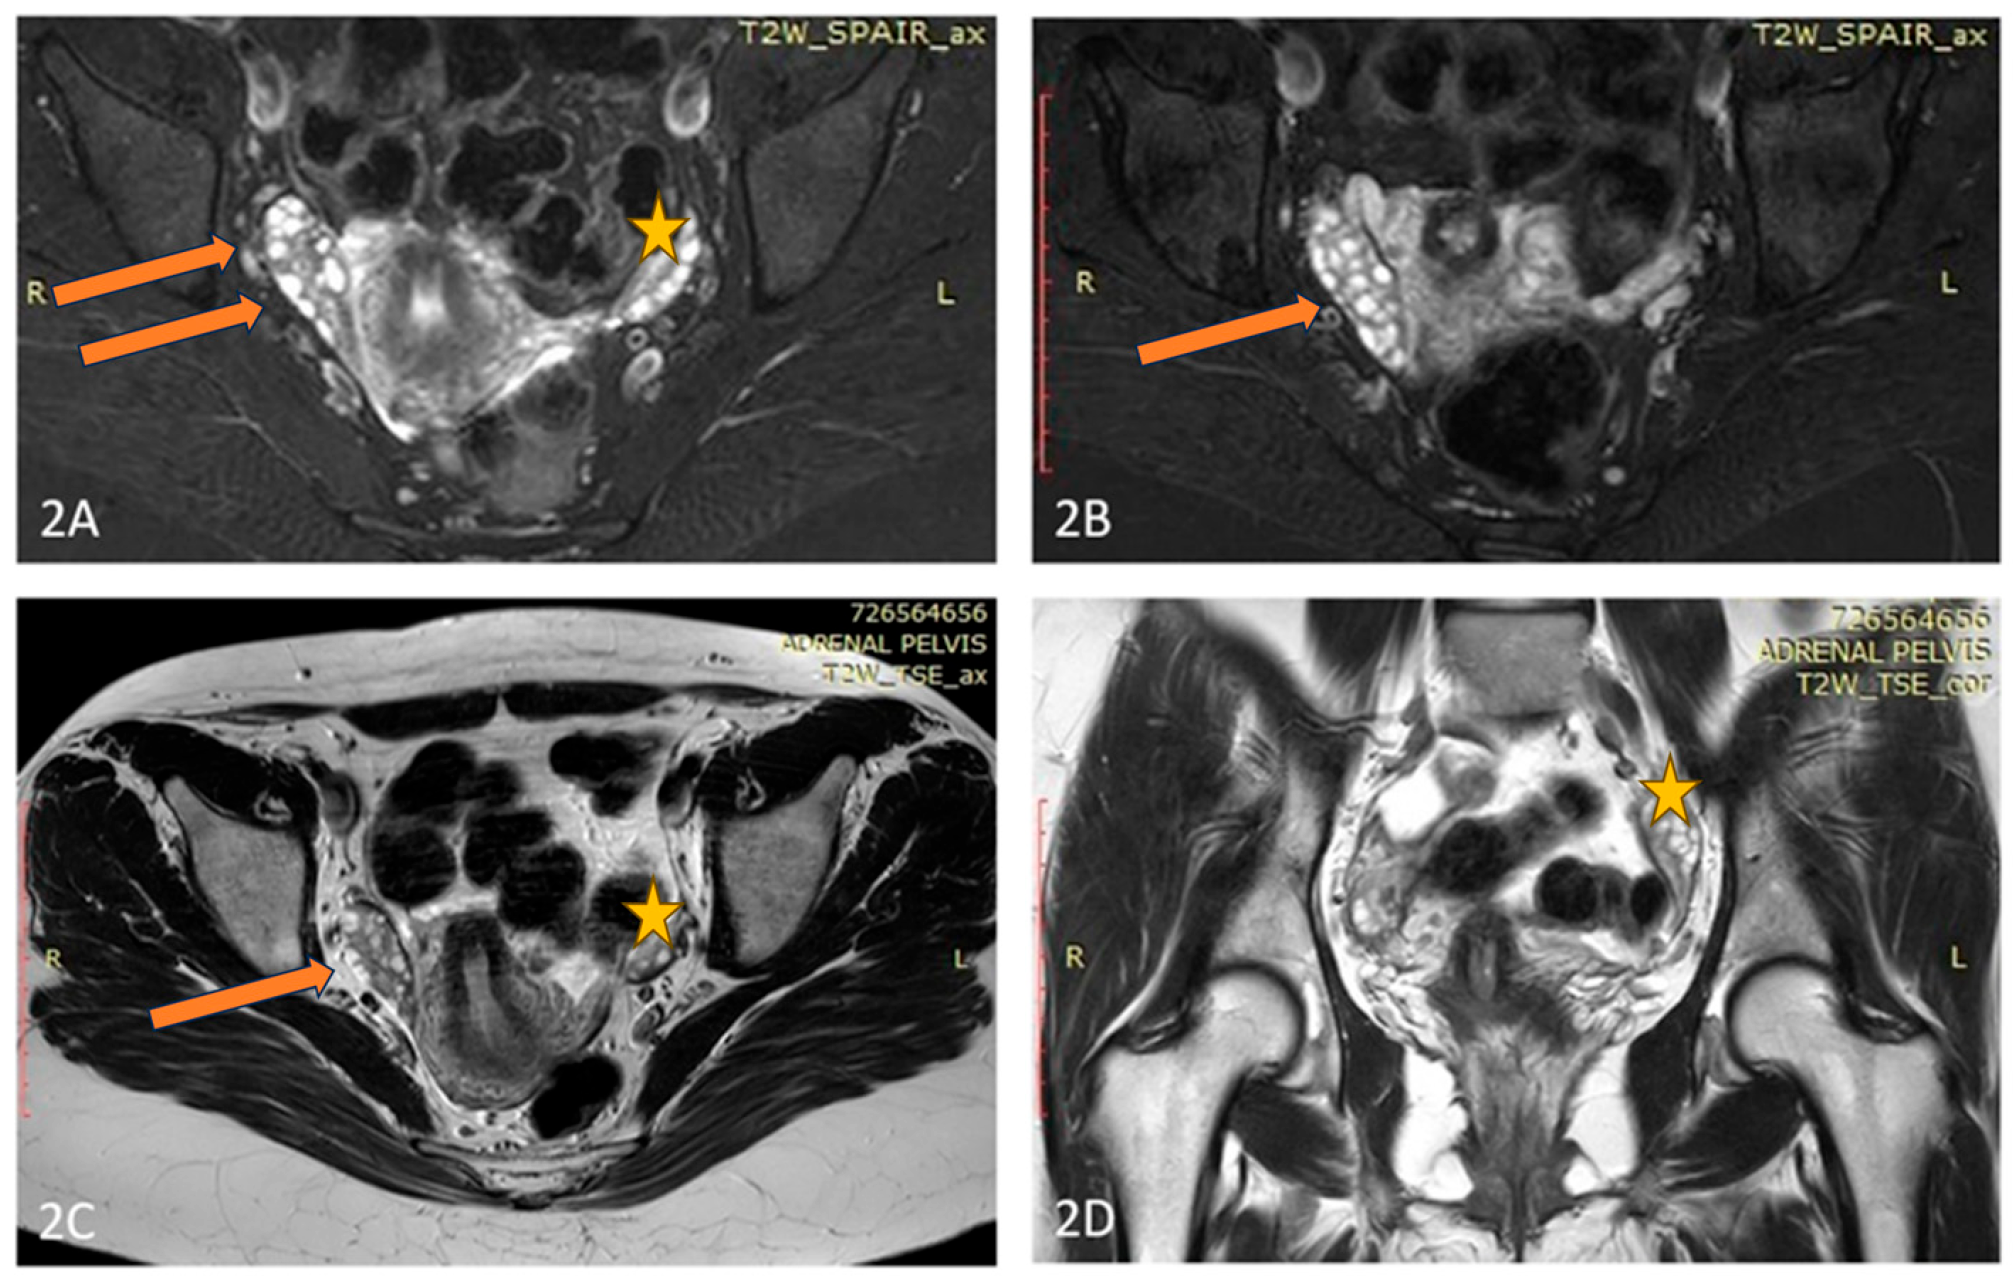

A pelvic ultrasound showed an increased size of the right ovary without any evidences of tumor mass. An MRI of the abdomen and pelvis also did not reveal any suspicious formation but proved the doubled size of the right ovary compared to the left one (Figure 2). Tumor markers were negative. Because of abnormal uterine bleeding, a therapy with oral contraceptives was introduced with a rapid alleviation of symptoms. No substantial decrease of AMH levels were found under hormonal therapy. An MRI of the pituitary showed a 6 mm-large pituitary microadenoma, without overt hormonal secretion. Additionally, a cytogenetic study on a heparin-blood sample was performed, showing a karyotype 45,XX,der(14;21)(q10;q10) with balanced Robertsonian translocation. The patient was referred for genetic counselling, where possible reproductive risks were explained. A segregation analysis in the family revealed the paternal origin of the translocation between chromosomes 14 and 21. The patient conceived on the first cycle of ovulation induction. Unfortunately, after amniocentesis was performed, a fetal trisomy 21 with mosaic ratio 14% was detected and the family decided to terminate the pregnancy. Thereafter, the dysfunctional uterine bleeding episodes persisted, as well as the chronic anovulation.

Figure 2. (AD) Axial T2 Fat Sat (A,B), Axial T2 (C), and Coronal T2 (D) images of the patient demonstrate an elongated, fused double right-sided ovary (arrow), and normal size and appearance of the left ovary (star).